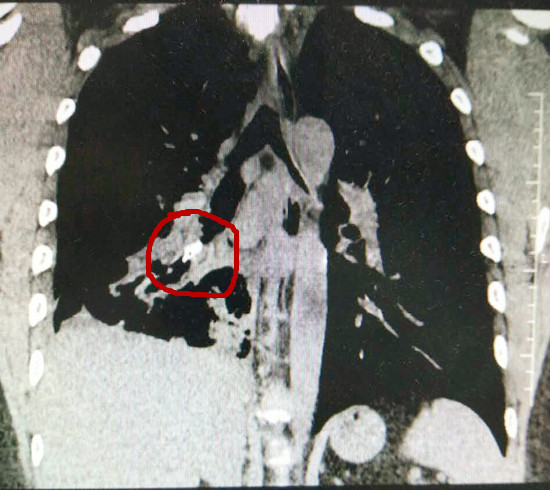

谢先生入住市五邑中医院肺病科一区后,主诊医生彭景钦副主任医师随即为其安排了一次“绿色通道”检查。通过该院清晰度极高的宝石CT扫描肺部,结果惊讶地发现谢先生的右肺在大片炎症“掩盖下”隐藏着一小块硬度很高的病灶, 彭景钦副主任医师瞬即将“新发现”向科主任范发才作了汇报。

(胸部CT重建显示右下肺支气管内高密度异物)

该院肺病科学科带头人范发才主任及时介入了解病情,详细阅读了CT片,判断谢先生的病情诱因实为异物误吸进入右肺支气管所致。尽管距离下班不足半小时,范发才主任仍当机立断指挥所属科室专家团队各就各位为谢先生施行支气管镜下行异物钳取术投入准备,力争早一秒解除患者痛苦。